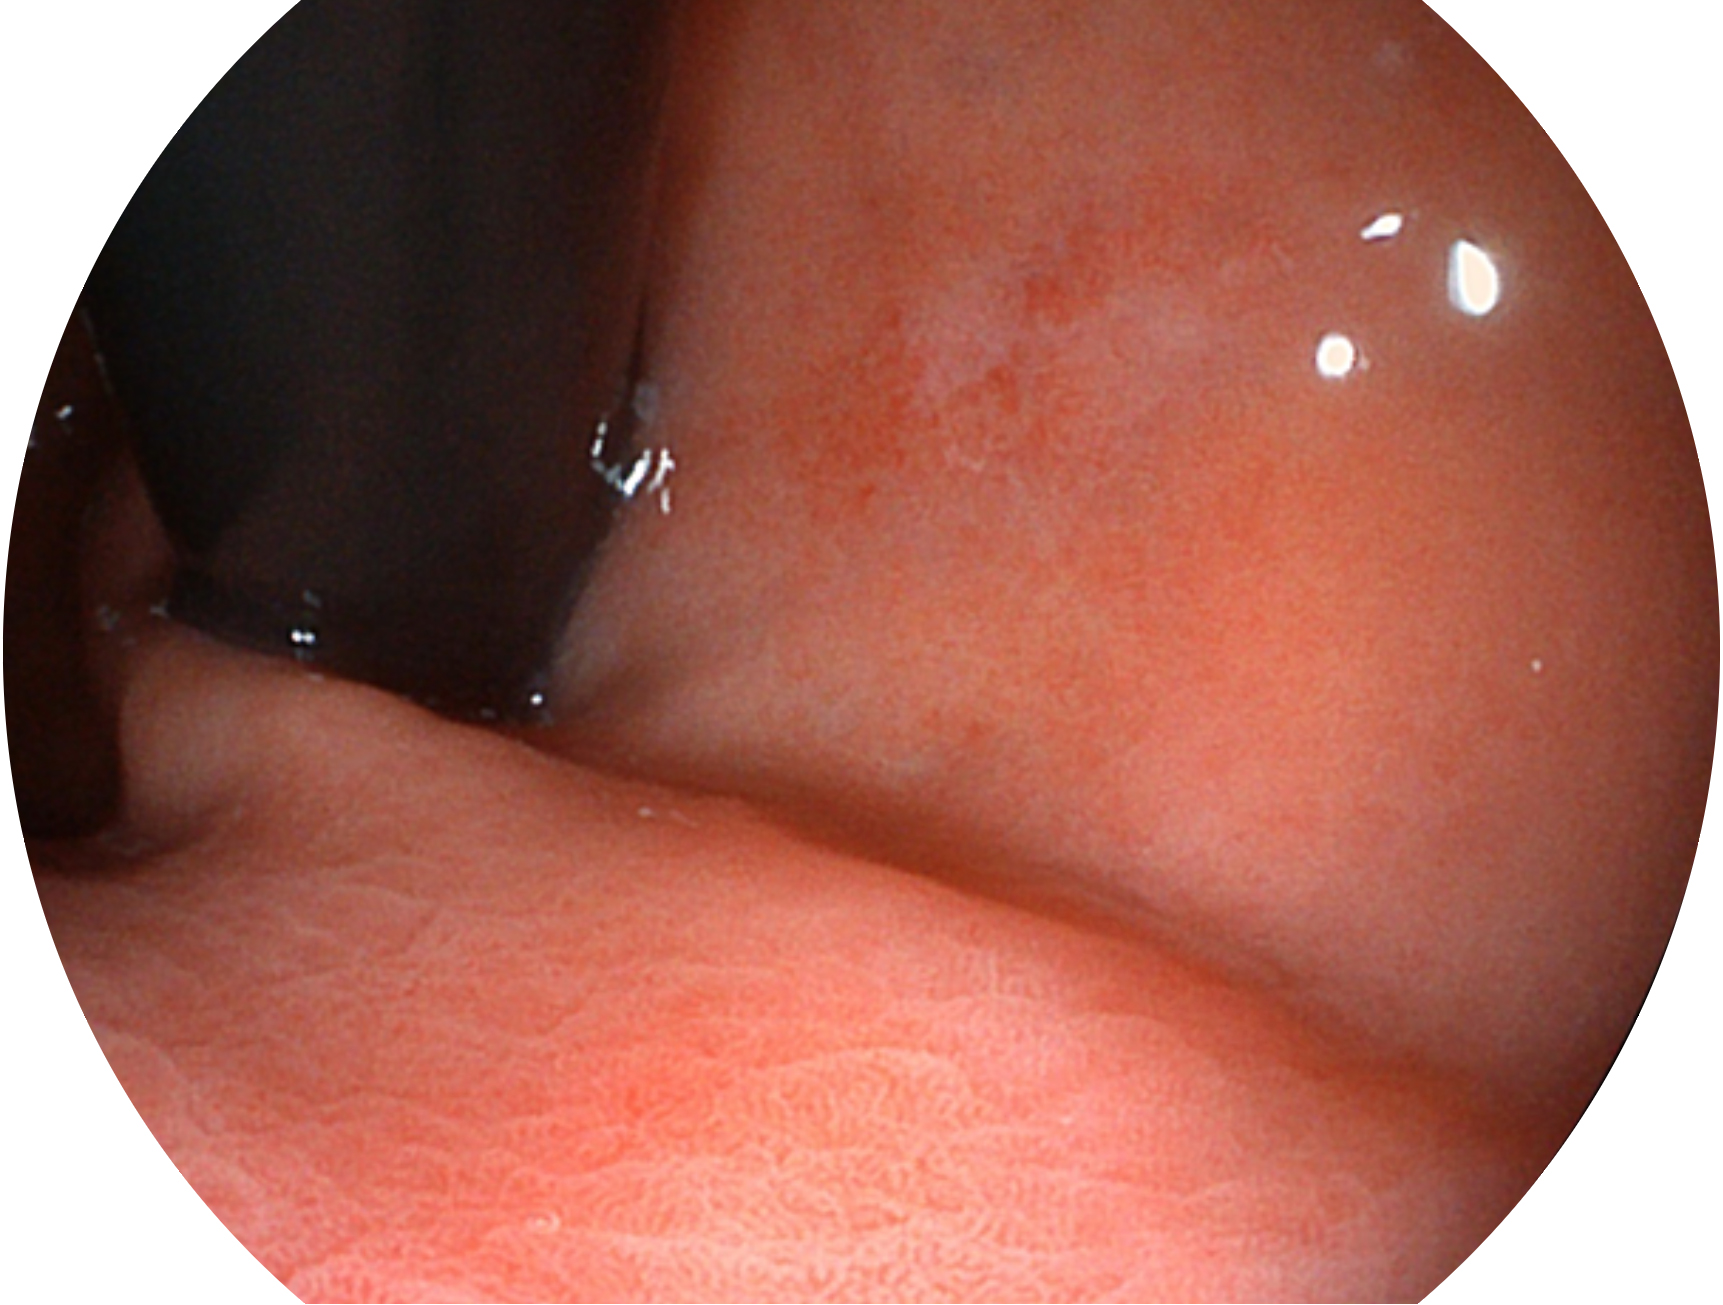

• 白光图像 SFI图像

SFI技术是结合特定光谱照明与数字光谱滤波,实现高亮度特殊光成像。染色模式下,不改变粘液、食物残渣、粪液等基本颜色,在保持与白光照明相似的图像色调的同时突显了图像颜色的红白对比度,且在远距离观察的情况下具备与普通白光模式相同的图像亮度,有助于消化道疾病的大范围扫查和早癌筛查。